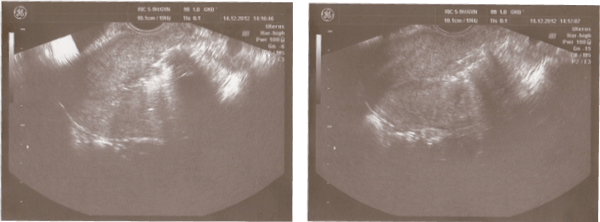

Three months later a recurrent hospitalization in N.I. Pirogov City Clinical Hospital No.1 was followed due to a heavy bloody discharge from the genital tract. The patient complained of two heavy menstrual periods after UAE. According to the ultrasound investigation of the organs of lesser pelvis, the submucosal fibroid was descended to the lower third of the uterus. This time it was 10.5cm×6.5cm×7.9 cm in size. Intranodular and perinodular blood flow were well pronounced on the Colour Doppler scan (Figure1).

Figure 1: Ultrasound investigation of the uterus and uterine fibroid after using UAE for the first time